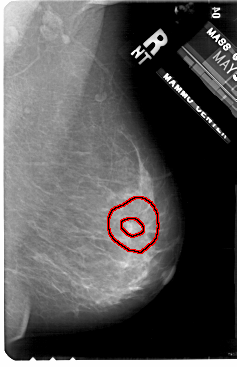

A_1906_1.LEFT_MLO

FILE: A_1906_1.LEFT_MLO.OVERLAY

TOTAL_ABNORMALITIES 1

ABNORMALITY 1

LESION_TYPE CALCIFICATION TYPE PLEOMORPHIC DISTRIBUTION SEGMENTAL

ASSESSMENT 4

SUBTLETY 3

PATHOLOGY MALIGNANT

TOTAL_OUTLINES 1

BOUNDARY